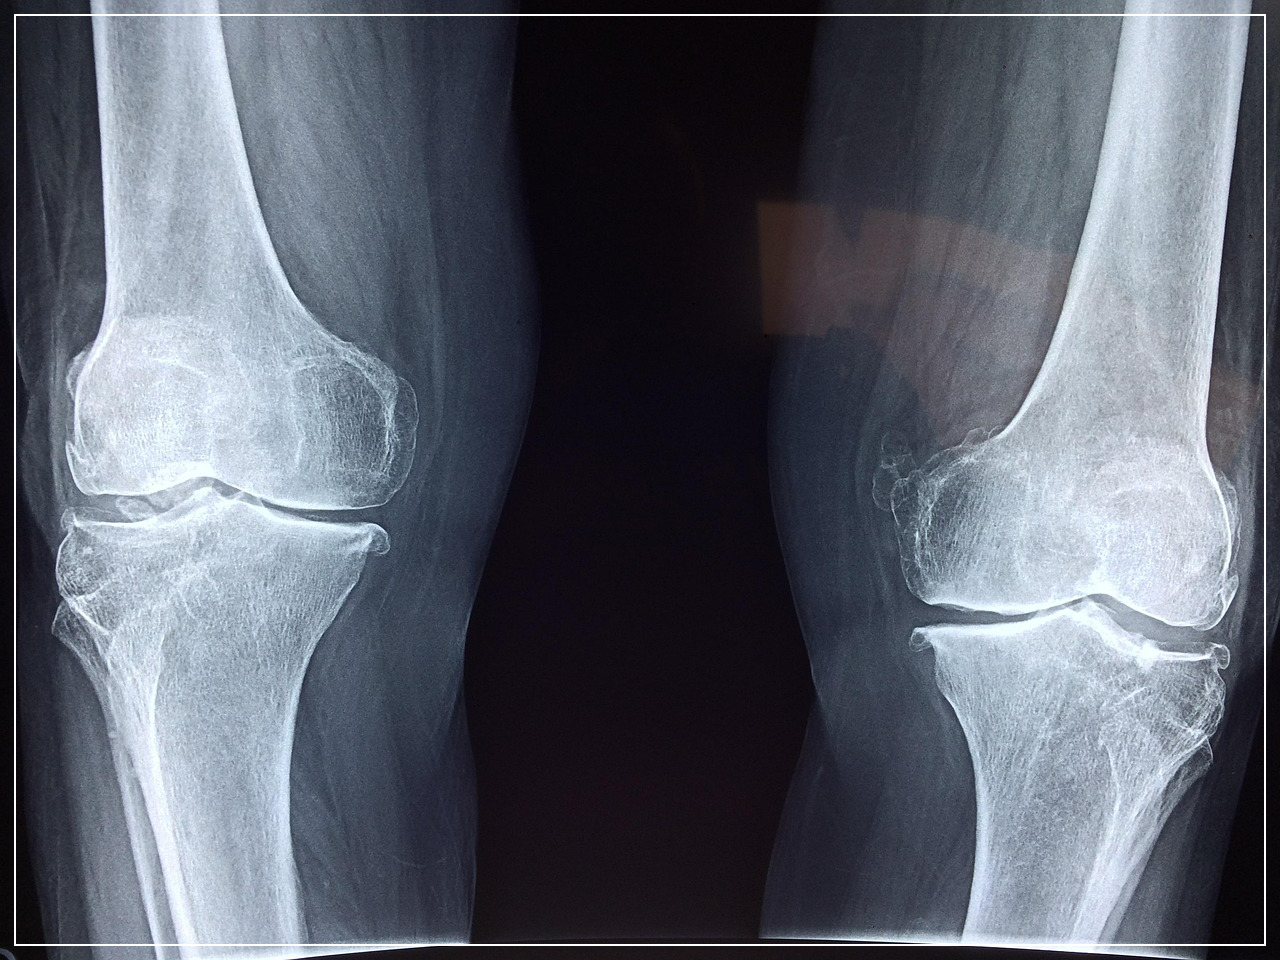

40~60대에 접어들면 “무릎이 뻐근하다”, “팔이 잘 안 올라간다”는 말이 자연스레 나옵니다.

이는 단순한 노화가 아닌 ‘관절 기능 저하’의 신호일 수 있습니다.

1. 중년의 관절, 왜 더 뻣뻣하고 아픈가요?

• 연골 감소 → 마찰 증가

• 윤활액 부족 → 뻑뻑함 유발

• 운동량 감소 → 가동 범위 축소

• 체중 증가 → 무릎 부담 가중